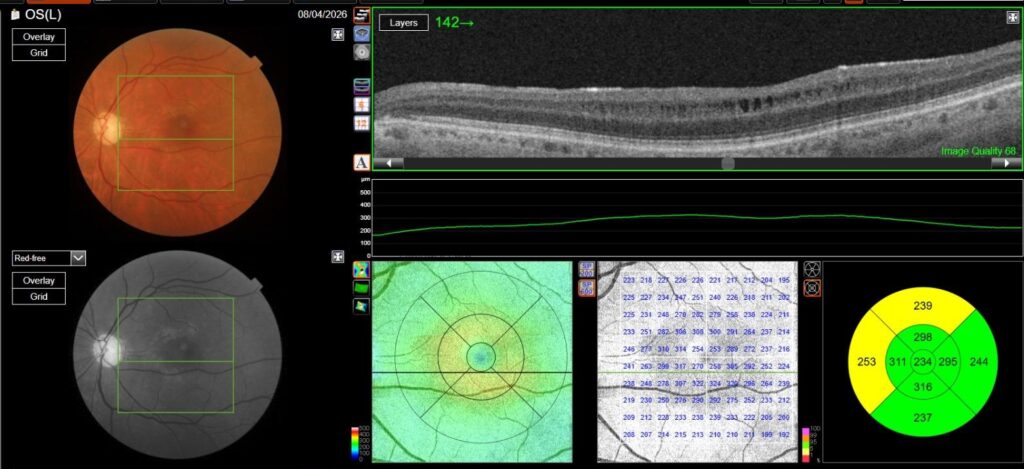

OCT in OD was normal, while in OS it showed multiple, well-defined small hyporeflective cystic spaces localized to the inner retinal layer (INL) in the perifoveal area, alongside with extreme thinning of the retinal nerve fiber layer (RNFL), whose profile and reflectivity were barely noticeable.

Optic Disc OCT with RNFL thickness quantification was performed as well; while in OD it revealed a minimal RNFL defect, in OS it showed extensive and severe RNFL thinning in all sectors, which was also confirmed on GCL+/GCL++ analysis by means of a 3D macula scan.

OCT-A was also performed in OS and, as expected, turned out to be negative. This also allowed an OCT en-face acquisition and subsequent segmentation at INL, which clearly showed the perifoveal distribution pattern of the INL cystic spaces previously found on b-scan OCT, with complete encompassing of the fovea and relative predominance in the inferior macular region.

That being said, our case allows for some interesting considerations: on one hand, MME was only found in her left eye, where the optic neuropathy was more severe, thus confirming the available literature data; on the other hand, however, en-face OCT clearly shows involvement of both inferior and superior hemiretina, although a relatively prevalent involvement of inferior hemiretina can be observed. This could either be explained by a more diffuse and severe RNFL and GC involvement, as demonstrated by both RNFL and GCC analysis, or by cohexistance of other, previously unrecognized optic neuropathy in addition to glaucomatous optic neuropathy. Lastly, no ERM was found on OCT, thus complying with evidence suggesting that vitreomacular traction may play a role in MME formation, but mainly as a concurrent cause rather than a primary pathogenetic element.